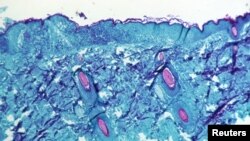

ကမ္ဘာတဝန်းမှာ Monkeypox လို့ခေါ်တဲ့ မျောက်ကနေ ကူးစက်တဲ့ ကျောက်ရောဂါတွေ ပိုပြီးတော့ အဖြစ်များလာလိမ့်မယ်လို့ ခန့်မှန်းကြောင့် ကမ္ဘာ့ကျန်းမာရေးအဖွဲ့ချုပ် (WHO) က ပြောလိုက်ပါတယ်။

မျောက်ကနေကူးစက်တဲ့ ကျောက်ရောဂါဟာ ပုံမှန်အားဖြင့်တော့ ရောဂါသိပ်ပြင်းထန်လေ့ မရှိဘဲ၊ အာဖရိက အနောက်ပိုင်း နဲ့ အလယ်ပိုင်း ဒေသတွေမှာ ဖြစ်လေ့ရှိတာ ဖြစ်ပါတယ်။ ဒီရောဂါဟာ အနီးကပ်နေထိုင်သူတွေကြားမှာ ကူးစက်တတ်တာကြောင့် သီးခြားခွဲနေတာတွေနဲ့ တကိုယ်ရေ ပတ်ဝန်းကျင်သန့်ရှင်းမှုတွေ လုပ်ခြင်းအားဖြင့် ရောဂါကို အတော်လေး အလွယ်တကူ ထိန်းချုပ်နိုင်တာ ဖြစ်ပါတယ်